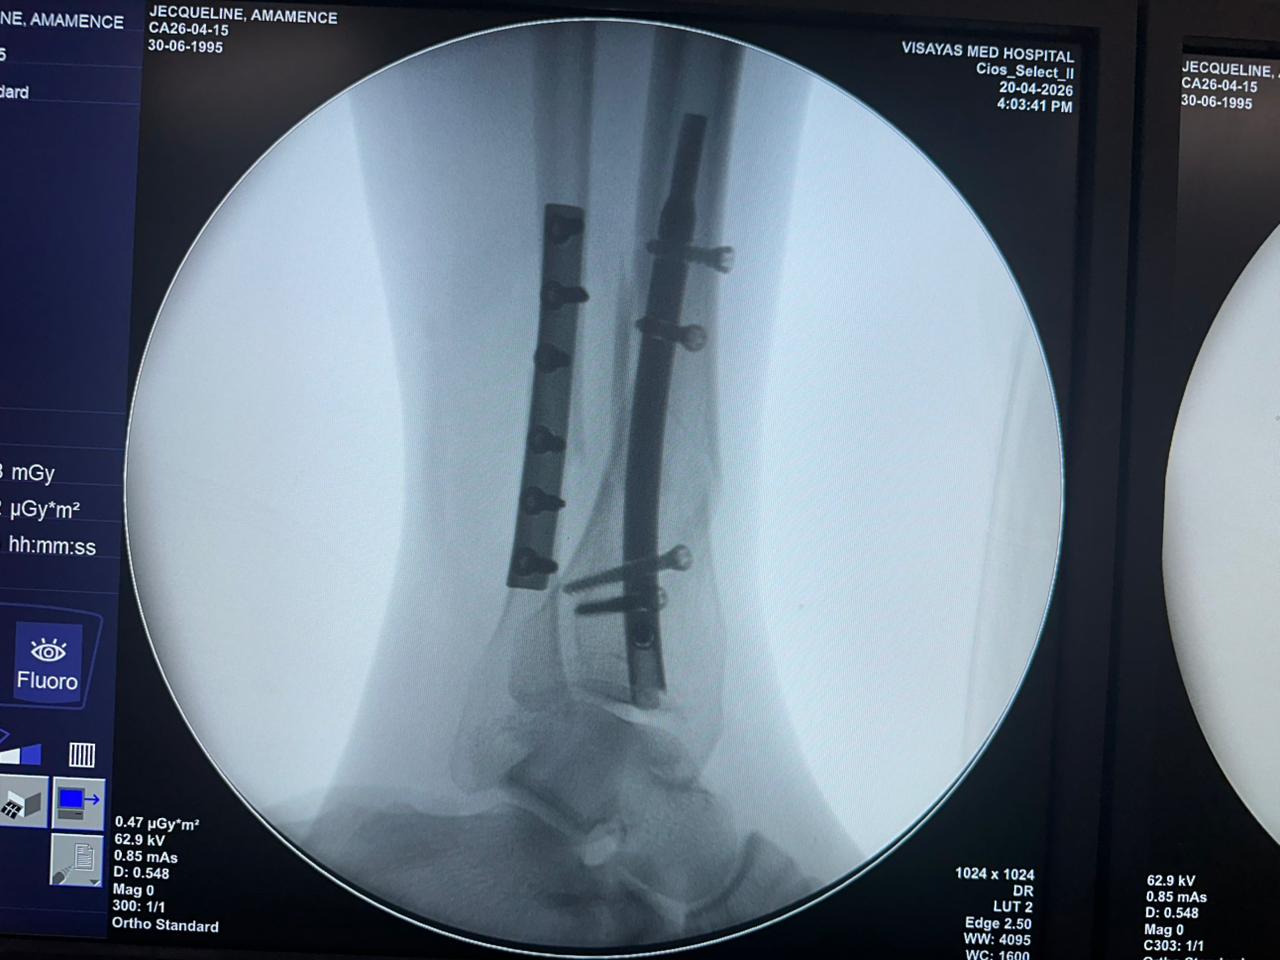

Estudio de caso de fijación de clavo tibial distal con soporte de placa para peroné

Imágenes:

Radioscopia intraoperatoria con arco en C, vistas AP y lateral

Este caso involucró la fijación de la tibia distal utilizando un clavo tibial distal intramedular. La fluoroscopia intraoperatoria confirmó la posición del clavo, los tornillos de bloqueo distales y la fijación de la placa del peroné.

clavo-distal-tibial-caso-paciente-de-31-años-vista-lateral-czmeditech